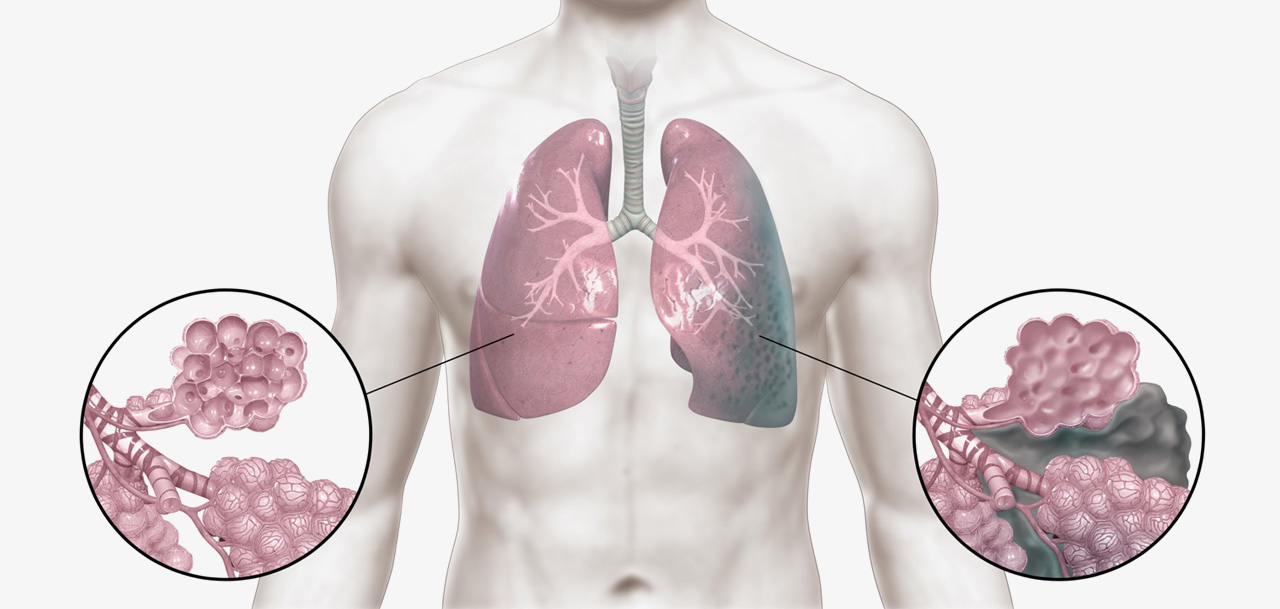

특발성폐섬유증과 같은 간질성폐질환은 예후가 좋지 못하다고 알려진 병입니다. 하지만 한약 치료를 통해 이 병을 극복하려는 노력이 진행되고 있습니다.